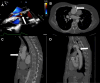

Objectives: Reoperative cardiac surgery is technically demanding. We describe the case of a 57-year-old woman found to have an ascending aortic pseudoaneurysm invading the sternum at the time of her sixth cardiac reoperation.

Take-home messages: This case describes the operative management of a patient undergoing a sixth sternotomy with an aortic pseudoaneurysm invading the sternum. Although challenging, this case could be performed successfully with careful attention to preoperative imaging, planning, and team communication.